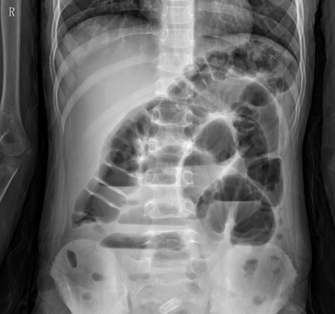

立位腹部X线平片如下图。

(4)立位腹部X线平片可见多个气液平面。(1分)